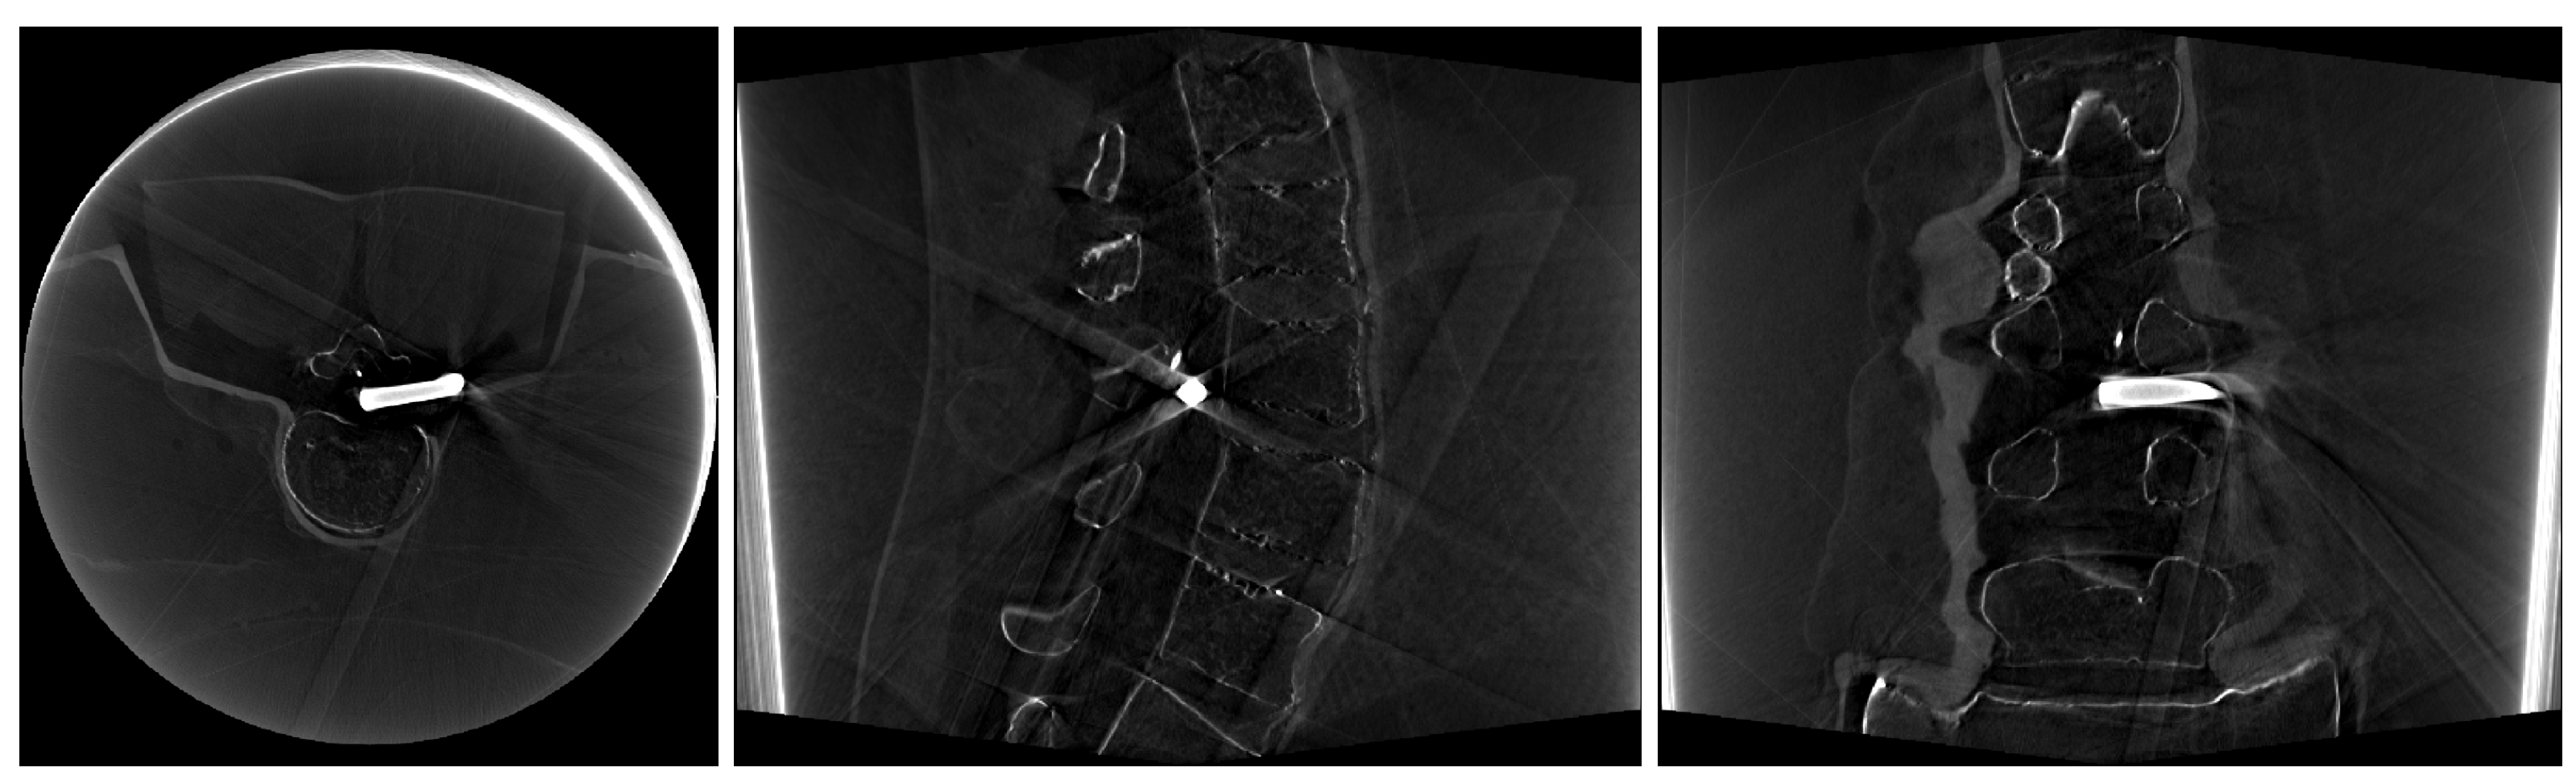

2.4. Image Data